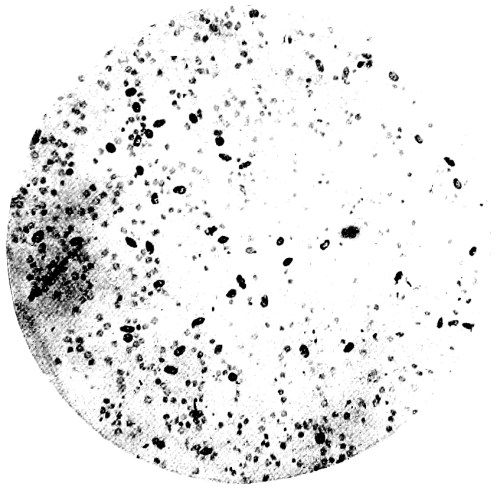

9. Measurement of Blood Corpuscles (sheep) 97

10. Photo-micrograph of Red Blood Corpuscles from Domestic Fowl 99

11. Photo-micrograph of Blood Corpuscles of Fish 99

12. Photo-micrograph of Blood Corpuscles from a Dried Stain of the Blood of a Cod-fish 100

13. Photo-micrograph of a Frog‘s Blood showing oval nucleated Red Corpuscles 101

14. Photo-micrograph of Crystals of Hæmin 102